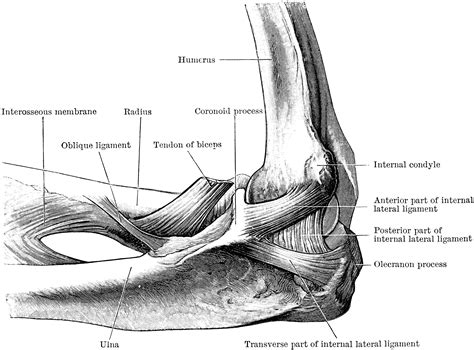

The elbow joint is stabilized by several ligaments, which provide support and prevent excessive movement. The main ligaments include:

• Ulnar Collateral Ligament (UCL): Located on the medial side of the elbow, it prevents excessive valgus stress (outward bending).

• Radial Collateral Ligament (RCL): Located on the lateral side of the elbow, it prevents excessive varus stress (inward bending).

• Annular Ligament: Wraps around the head of the radius, holding it in place against the ulna.

• elbow bones diagram

• elbow joint anatomy labeled

• elbow diagram

• elbow joint structure diagram